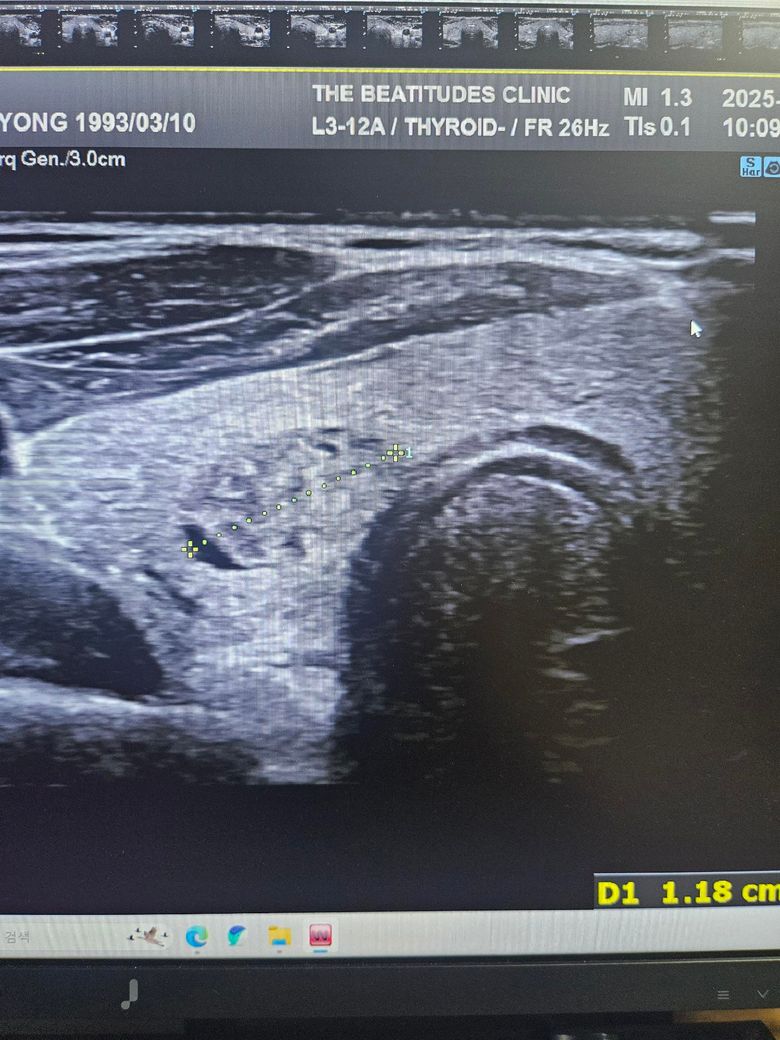

갑상선초음파하고 세침검사 권유받았는데 위의 세개의 사진은 같은 혹이 맞는건가요? 1개 있다고 얘기해줘서 봤는데 사이즈가 이렇게나와서 가로 세로 폭 값인건지 여쭤보고싶습니다

• 3번 째 사진

첫번째 사진과 세번째 사진의 경우 같은 결절로 보입니다.

단지 3번째 사진의 경우 크기가 기재되어 있지 않기 때문에

크기만으로 따진다면 이는 애매하다 할 수 있겠습니다.

초음파에서 첫번째, 세번째 사진의 급성 연골 오른쪽에 위치한 오른쪽 갑상선에 동그란 혹이 관찰되며 사진으로는 사이즈를 정확하게 구하기 어렵지만 1.5 cm 이상으로 보이며 혹 안에 균질하지 않은 모습으로 악성 혹은 양성이라고 해도 정기적으로 관찰해야 하는 종양으로 보여 조직 검사를 받는 것은 필요한 것으로 보입니다. 갑상선 종양은 다른 종양에 비해 예후가 좋아 적절한 치료를 받으면 대부분 완치가 가능합니다